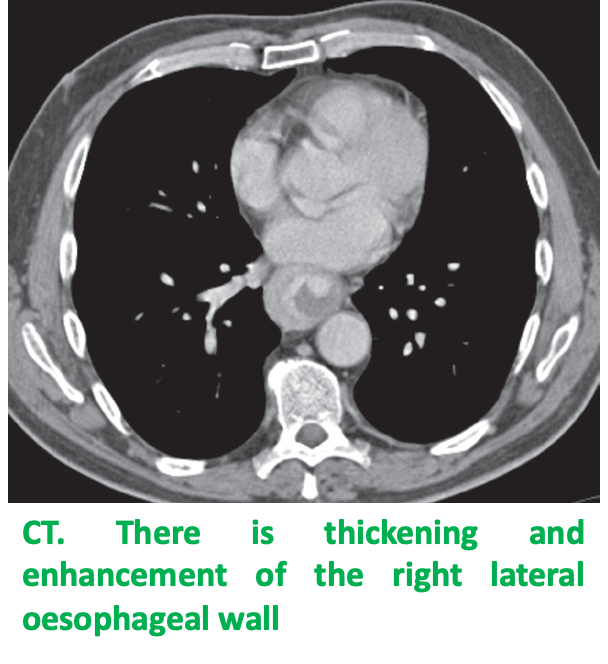

Malignant stricture DYSPHAGIA:

produce abrupt narrowing. It is irregular and associated with mucosal destruction. Z